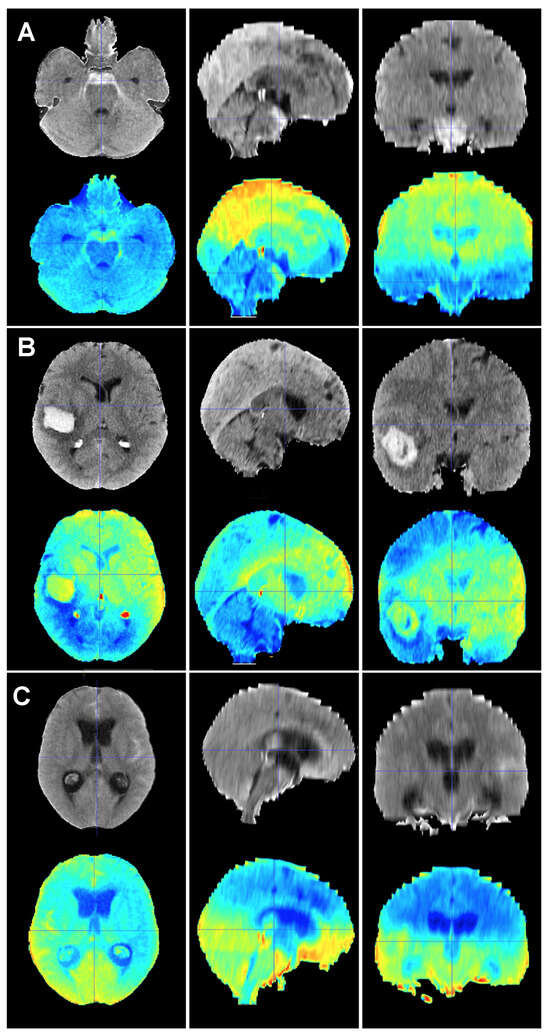

Figure 6.

Baseline CT scan (upper row) and gradient-weighted class activation mapping or Grad-CAM (lower row) for three patients (A–C) from the test cohort who died as a result of a subarachnoid hemorrhage (SAH). These maps visually illustrate the areas the model considered to allocate patients into the “dead” group. Grad-CAM maps show that posterior fossa and intraventricular and cisternal blood might be relevant areas or items to consider in order to classify patients as dead. (A) A 51-year-old male who suffered a SAH due to the rupture of a left middle cerebral artery aneurysm. The patient initially presented with a WFNS grade 2, but abruptly deteriorated to a WFNS grade 5 requiring emergent surgical treatment. The patient died on postoperative day 56 as a consequence of both systemic and neurological complications. (B) A 70-year-old female who was diagnosed with a SAH caused by a right posterior communicating artery aneurysm who died 40 days after her admission due to a combination of factors, including delayed cerebral ischemia, meningitis and pneumonia. (C) A 78-year-old male with a SAH caused by an anterior communicating artery who was admitted to the hospital with a WFNS grade 5 and an mF grade 4 who died the next day after the event.